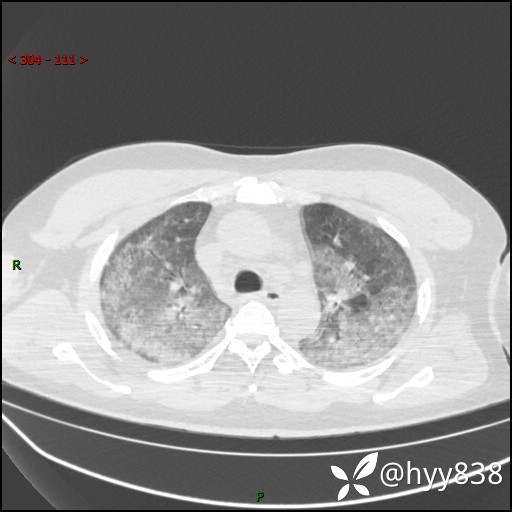

辅助检查:CT

临床诊断:间质性肺炎

第二次CT(7天后)